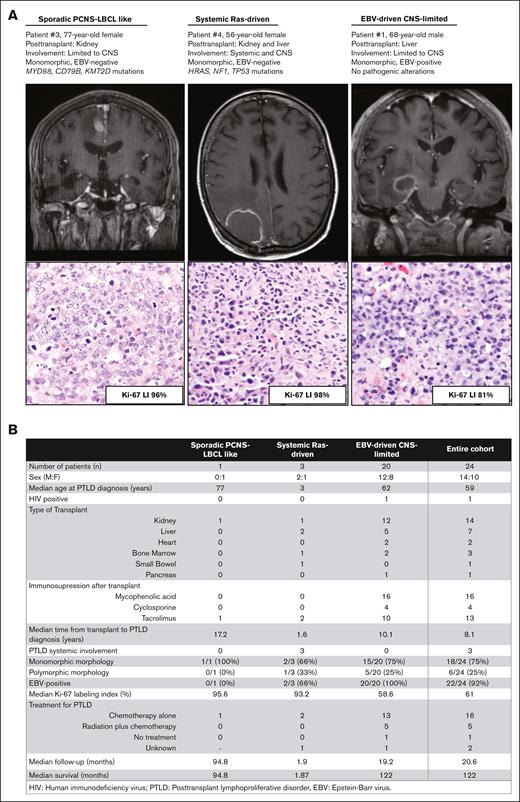

Clinical and pathologic features of the 3 identified types of PTLD involving the CNS. (A) Preoperative T1-weighted postcontrast magnetic resonance imaging and hematoxylin and eosin–stained sections from representative patients with sporadic PCNS-LBCL–like, systemic Ras-driven, and EBV-driven CNS-limited PTLD-CNS showing intraparenchymal mass lesions with contrast enhancement and significant edema in the surrounding white matter. Ki-67 LI is shown. (B) Summary of clinical and pathologic features of the multiinstitutional cohort of patients with PTLD-CNS.

Here, we sought to investigate the clinical, pathologic, and molecular characteristics of PTLD-CNS to better identify factors that may be useful in risk stratification of this patient population. Through a multi-institutional collaboration, we assembled a cohort of 24 patients with PTLD-CNS (Figure 1; supplemental Tables 1 and 2). Twenty-one patients had undergone solid organ transplantation, and 3 had undergone bone marrow transplantation. Patient #22 had severe combined immunodeficiency and Nijmegen breakage syndrome, and patient #8 had Down syndrome. The remaining patients did not have any known innate immunodeficiency or tumor predisposition syndromes. The median time from organ transplant to development of PTLD-CNS was 8.1 years. Of 24 patients, 21 patients had PTLD with exclusive CNS involvement, whereas the other 3 patients also had PTLD at systemic sites (2 gastrointestinal and 1 nodal involvement) outside the CNS. The median age at time of PTLD-CNS diagnosis was 59 years (range, 2-77 years). Eighteen PTLD cases demonstrated monomorphic morphologic features resembling LBCL, whereas 6 PTLD cases demonstrated polymorphic morphology with variable composition of small-to-large sized B cells admixed with T cells and plasma cells (Figure 1A; supplemental Tables 3 and 4). Patients were treated with various combinations of dexamethasone, high-dose methotrexate, and rituximab, along with other accompanying agents in a subset. Five patients were additionally treated with radiotherapy. The median survival of all patients with PTLD-CNS was 122 months, and the 5-year and 10-year overall survival rates were 67.5% and 50.6%, respectively. The University of California San Francisco Institutional Review Board approved this study, which was conducted in accordance with the Declaration of Helsinki.